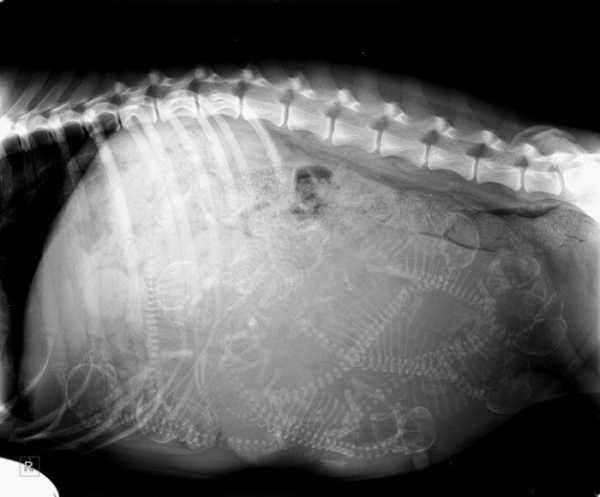

Рентгенівський знімок вагітного собаки